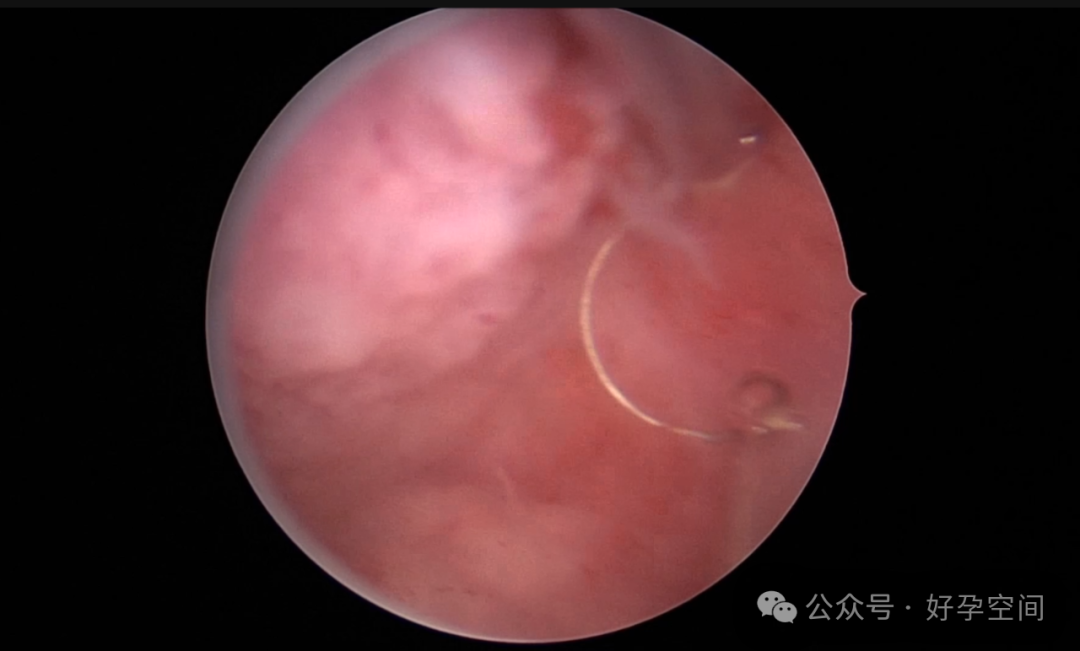

患者24岁,G6P3,顺产1次,双胎剖宫产1次。本次停经53天,计划外妊娠,行宫腔镜取胚及安环术。摘除胚胎后见宫腔右侧壁胚胎附着部位包块,约1.0cm*1.0cm*0.8cm,宫腔镜切除包块送病检,放置γ环一个,环两臂卷曲于右侧宫角,宫腔镜钩住环尾部下拉,上推节育环右臂,将环调整到正常位置。术后病检结果为“宫腔胎盘附着部位超常反应”。